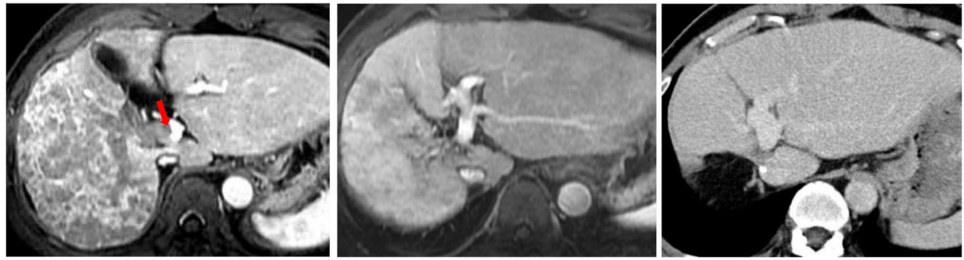

7例疾病稳定(SD)患者中42.9%术后未复发,中位OS达45个月,提示即使未达影像学缓解,HAIC仍可能改变肿瘤生物学行为。图1展示的Vp4患者经3周期HAIC后实现PR,术后5年无复发;图6则证实HAIC对肺转移灶的全身控制作用。